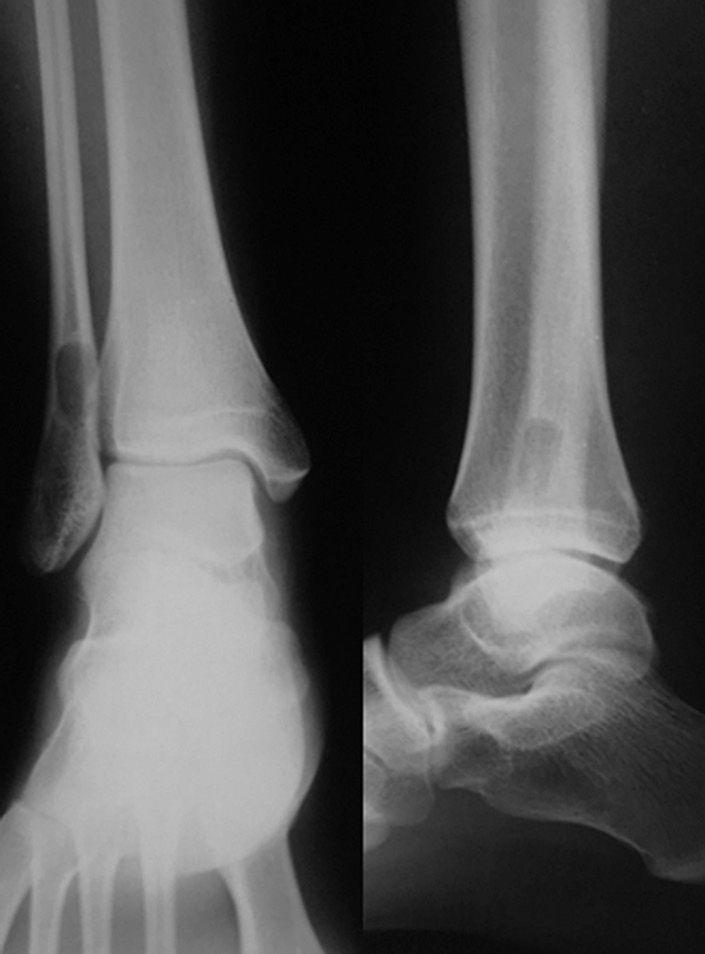

Ходьба при помощи костылей с дозированной нагрузкой на оперированную нижнюю конечность разрешена на 14-е сутки после оперативного вмешательства. На 21-е сутки после операции в зоне резекции костной кисты произошел перелом сохранившегося кортикального слоя малоберцовой кости без смещения (рис. 2). Иммобилизацию правой голени и стопы в постфрактурном периоде не осуществляли.

Рис. 2. Рентгенограмма. Состояние после оперативного лечения — краевой резекции пораженного отдела малоберцовой кости. Патологический перелом нижней трети малоберцовой кости, полость заполнена гранулами бета-трикальцийфосфата